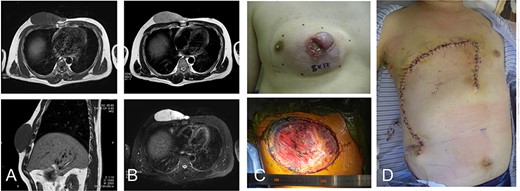

A 42-year-old man presented with a history of a mass on his right chest wall that gradually increased in size over 2–3 years. On physical examination, a protuberant hard, immobile elastic mass that appeared attached to the fascia was palpable on the anterior chest wall. Magnetic resonance imaging (MRI) revealed an 8 × 12-cm subcutaneous tumor. The tumor showed homogenous low-signal intensity on the T1-weighted image and high-signal intensity on the T2-weighted image (Fig. 1A and B). The tumor was attached to the fascia of the pectoralis major muscle.

42-year-old male with dermatofibrosarcoma protuberans in the chest wall. Magnetic resonance imaging shows the subcutaneous tumor with low-signal intensity on the T1-weighted image (A) and slightly high-signal intensity on the T2-weighted image (B-upper) and high-signal intensity on a T2-weighted fat-suppressed image (B-lower); photograph of ulcerated subcutaneous lesion with subcutaneous extension; after resection of the tumor with the surrounding tissue (C), the defect was reconstructed with a thoracoabdominal flap (D).

Histological examination of a needle biopsy specimen revealed a dermatofibrosarcoma protuberans. The tumor was resected along with the surrounding skin, subcutaneous tissue, and the underlying pectoralis major muscle, leaving a defect of 16 cm in the maximum diameter (Fig. 1C). The defect was reconstructed with a medially-based thoracoabdominal flap (Fig. 1D).

A vertical thoracoabdominal incision of the superficial layer of the skin was made on the lateral side of the defect. During elevation of the rotation flap, the perforators were preserved as much as possible. The lateral side of the flap was rotated medially to the edge of the defect. The patient’s shoulder showed free range of movement. The patient has remained free of tumor over a 4-year postoperative period.